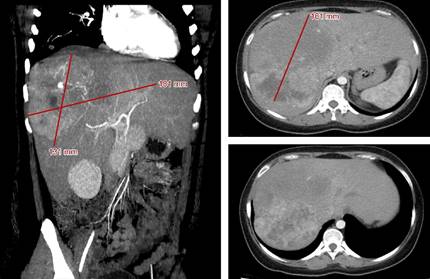

Se trata de paciente femenino de 20 años que acudió a urgencias con dolor abdominal difuso, náuseas y vómitos. La tomografía computarizada reveló una lesión heterogénea de 181 × 131 × 161 mm con múltiples lesiones satélites que abarcaban los segmentos V, VI, VII y VIII, así como nódulos pulmonares (Figura 1). La biopsia hepática central de la lesión reveló células neoplásicas con abundante citoplasma estromal granular y grandes áreas de fibrosis, CK7+, Hepar1+, compatibles con hepatocarcinoma fibrolamelar bien diferenciado. Fue considerado irresecable, por lo que se estableció un régimen paliativo consistente en tres sesiones de TACE con doxorrubicina cada 21 días a partir del 15 de junio de 2020, además de la participación en un protocolo con el uso de atezolizumab más bevacizumab iniciado en julio de 2020 y cumpliendo un total de 22 ciclos. Se logró controlar la enfermedad al mostrar una reducción del tamaño de la lesión del 26.7% (Tabla 1), la cual se mantuvo durante 18.13 meses. Tras la progresión, se valoró una segunda línea de tratamiento con regorafenib; sin embargo, ésta no logró concretarse, por lo que se iniciaron cuidados paliativos hasta el lamentable deceso de la paciente, alcanzando una supervivencia global de 22.23 meses.

Figura 1: Tomografía computarizada multifásica de estadificación de la paciente, realizada el 23 de mayo del 2020.